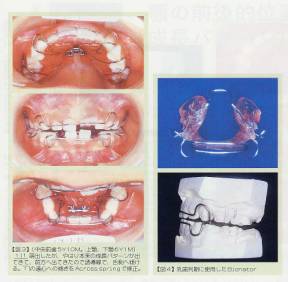

幼児(乳歯)の時からプレートを使って、大人の歯を初めから正しい位置に並べていく、という様子を説明しています。

↑まだ乳歯の頃です。

↑アゴの位置を正しくしています。

↑プレートを入れています。

↑永久歯が生えそろった頃です。